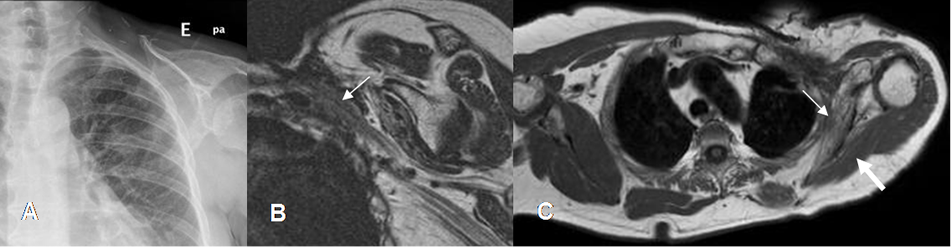

En la RM produce engrosamiento y realce de raíces, sin efecto de masa o lesión de tejidos blandos hipointensa en T1 y T2. (1, 2). (Fig 9 A, B y C).

Fig 9A. Cambios por radioTx.

A: Rx PA. Cambios PostQx y PostRTx, por el tratamiento de un liposarcoma en la pared torácica. Ausencia de la clavícula.

B: RM coronal en T2. Las raíces del plejo están engrosadas y rodeadas por tejido fibroso de señal intermedia.

C: RM axial en T1. Atrofia de los músculos infraespinoso (Flecha gruesa) y subescapular (Flecha delgada), el cual presenta además degeneración grasa. Estos cambios son secundarios a la denervación.